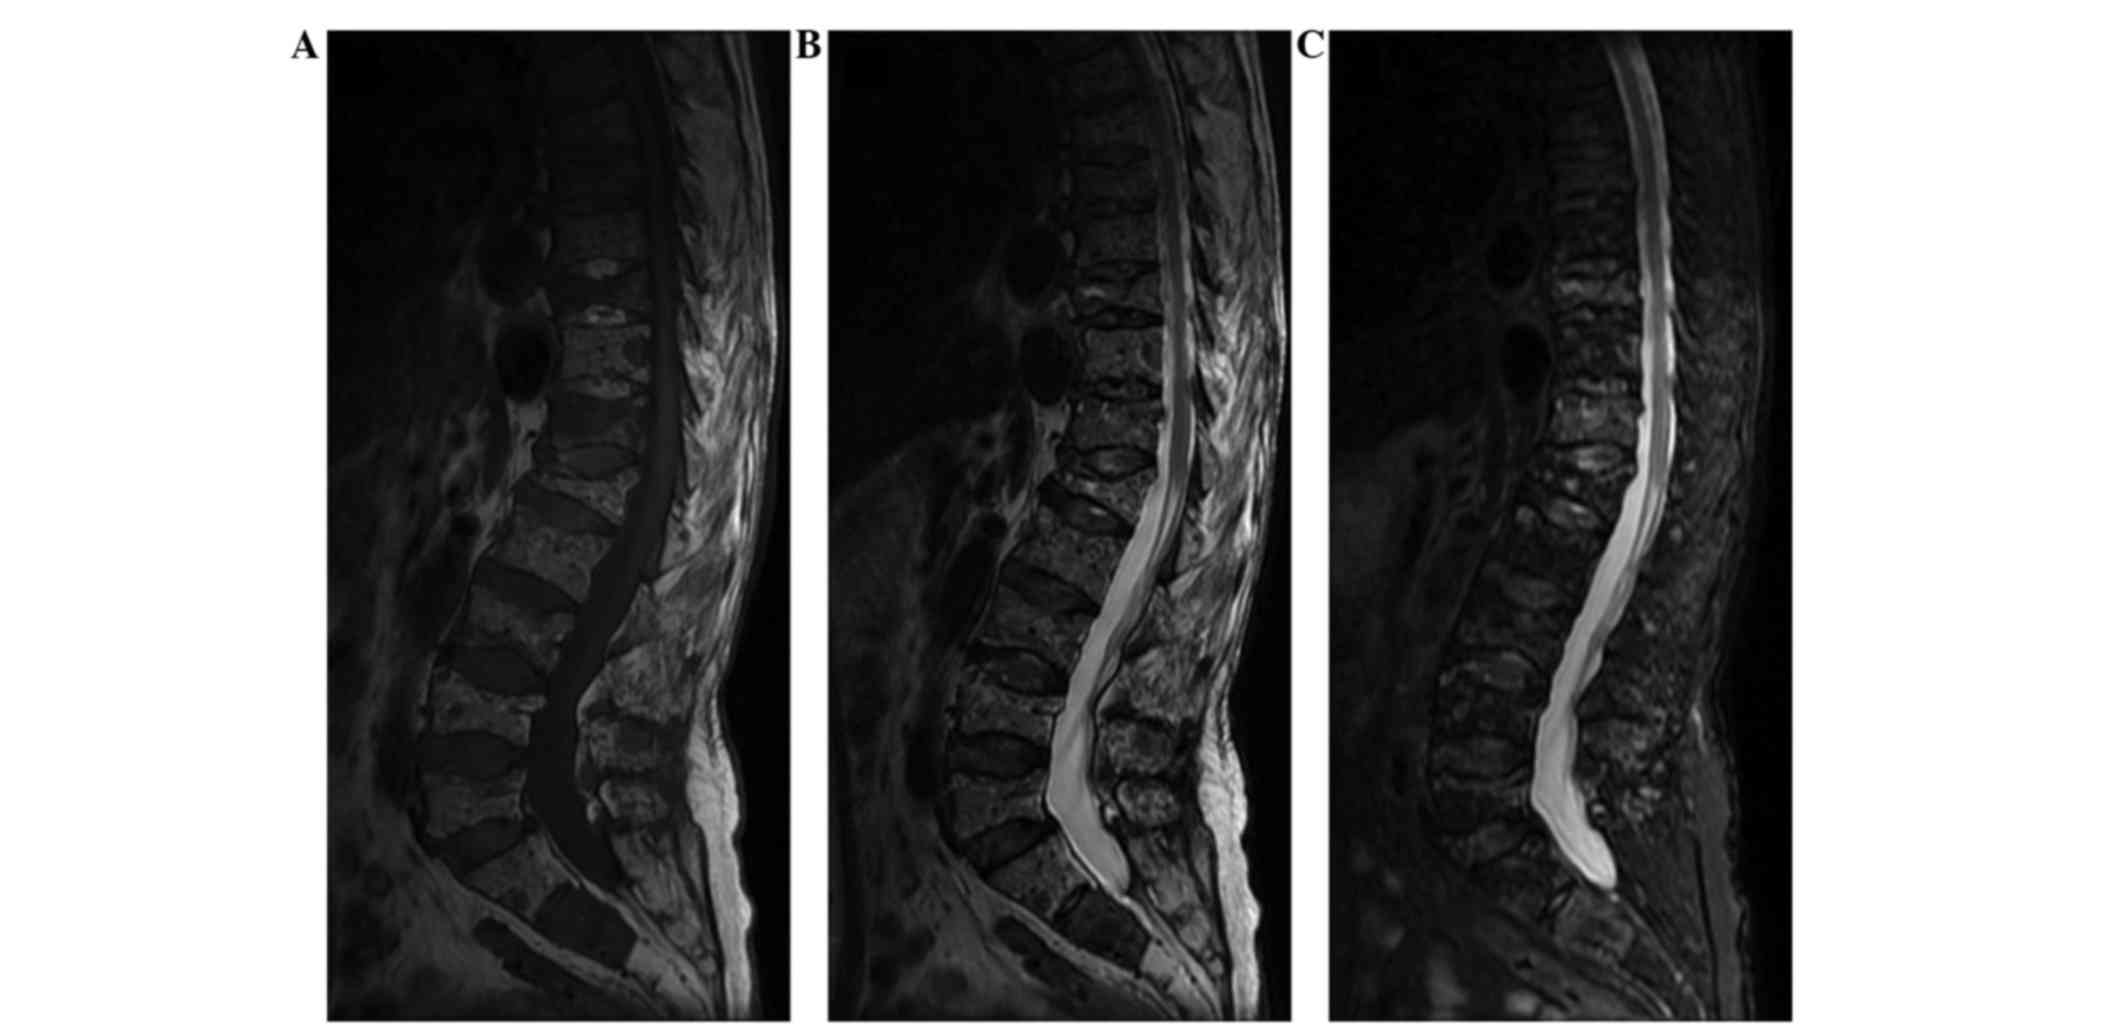

Case report

Figure 3.

Sagittal magnetic resonance imaging (MRI) showing a diffuse homogeneous abnormal signal with multiple vertebral compression fractures. (A) T1-weighted MRI revealing multiple vertebral compression fractures with a low signal intensity, the most severe of which were observed in T10 and L1. (B) T2-weighted MRI also indicating multiple vertebral fractures with a mildly high signal intensity. (C) On the short tau inversion recovery sequences, MRI revealed a diffuse homogeneous abnormal signal. A mildly high signal intensity was observed in T10 and T12.